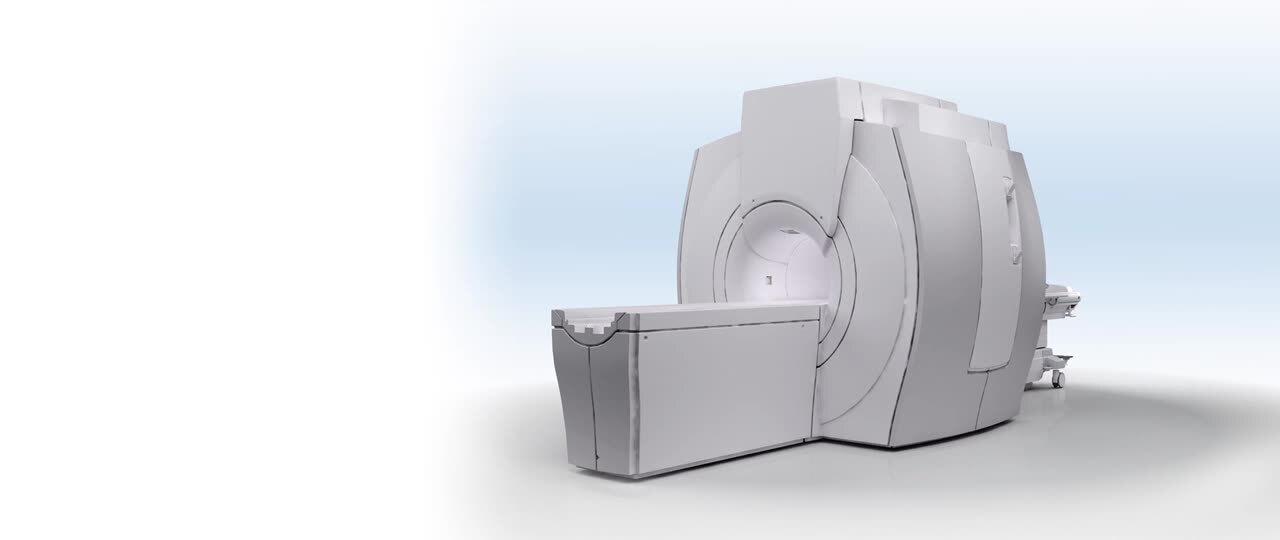

SIGNA Artist 1.5T MRI scanner provides 360-degrees of coil coverage, RF technology, and a direct digital interface with more channels. Patient-friendly design maximizes comfort and system utility, accommodating all types of patients and sizes with feet-first imaging. Combined with our industry-leading, deep-learning technology, AIR™ Recon DL, you can achieve consistent, exceptional images 50% faster;* streamlining workflows and reducing patient table time.

Our SIGNA Artist 1.5T wide-bore MRI scanner leverages groundbreaking technology that allows it to overcome common challenges. Surpass the unimaginable and make it the expected.